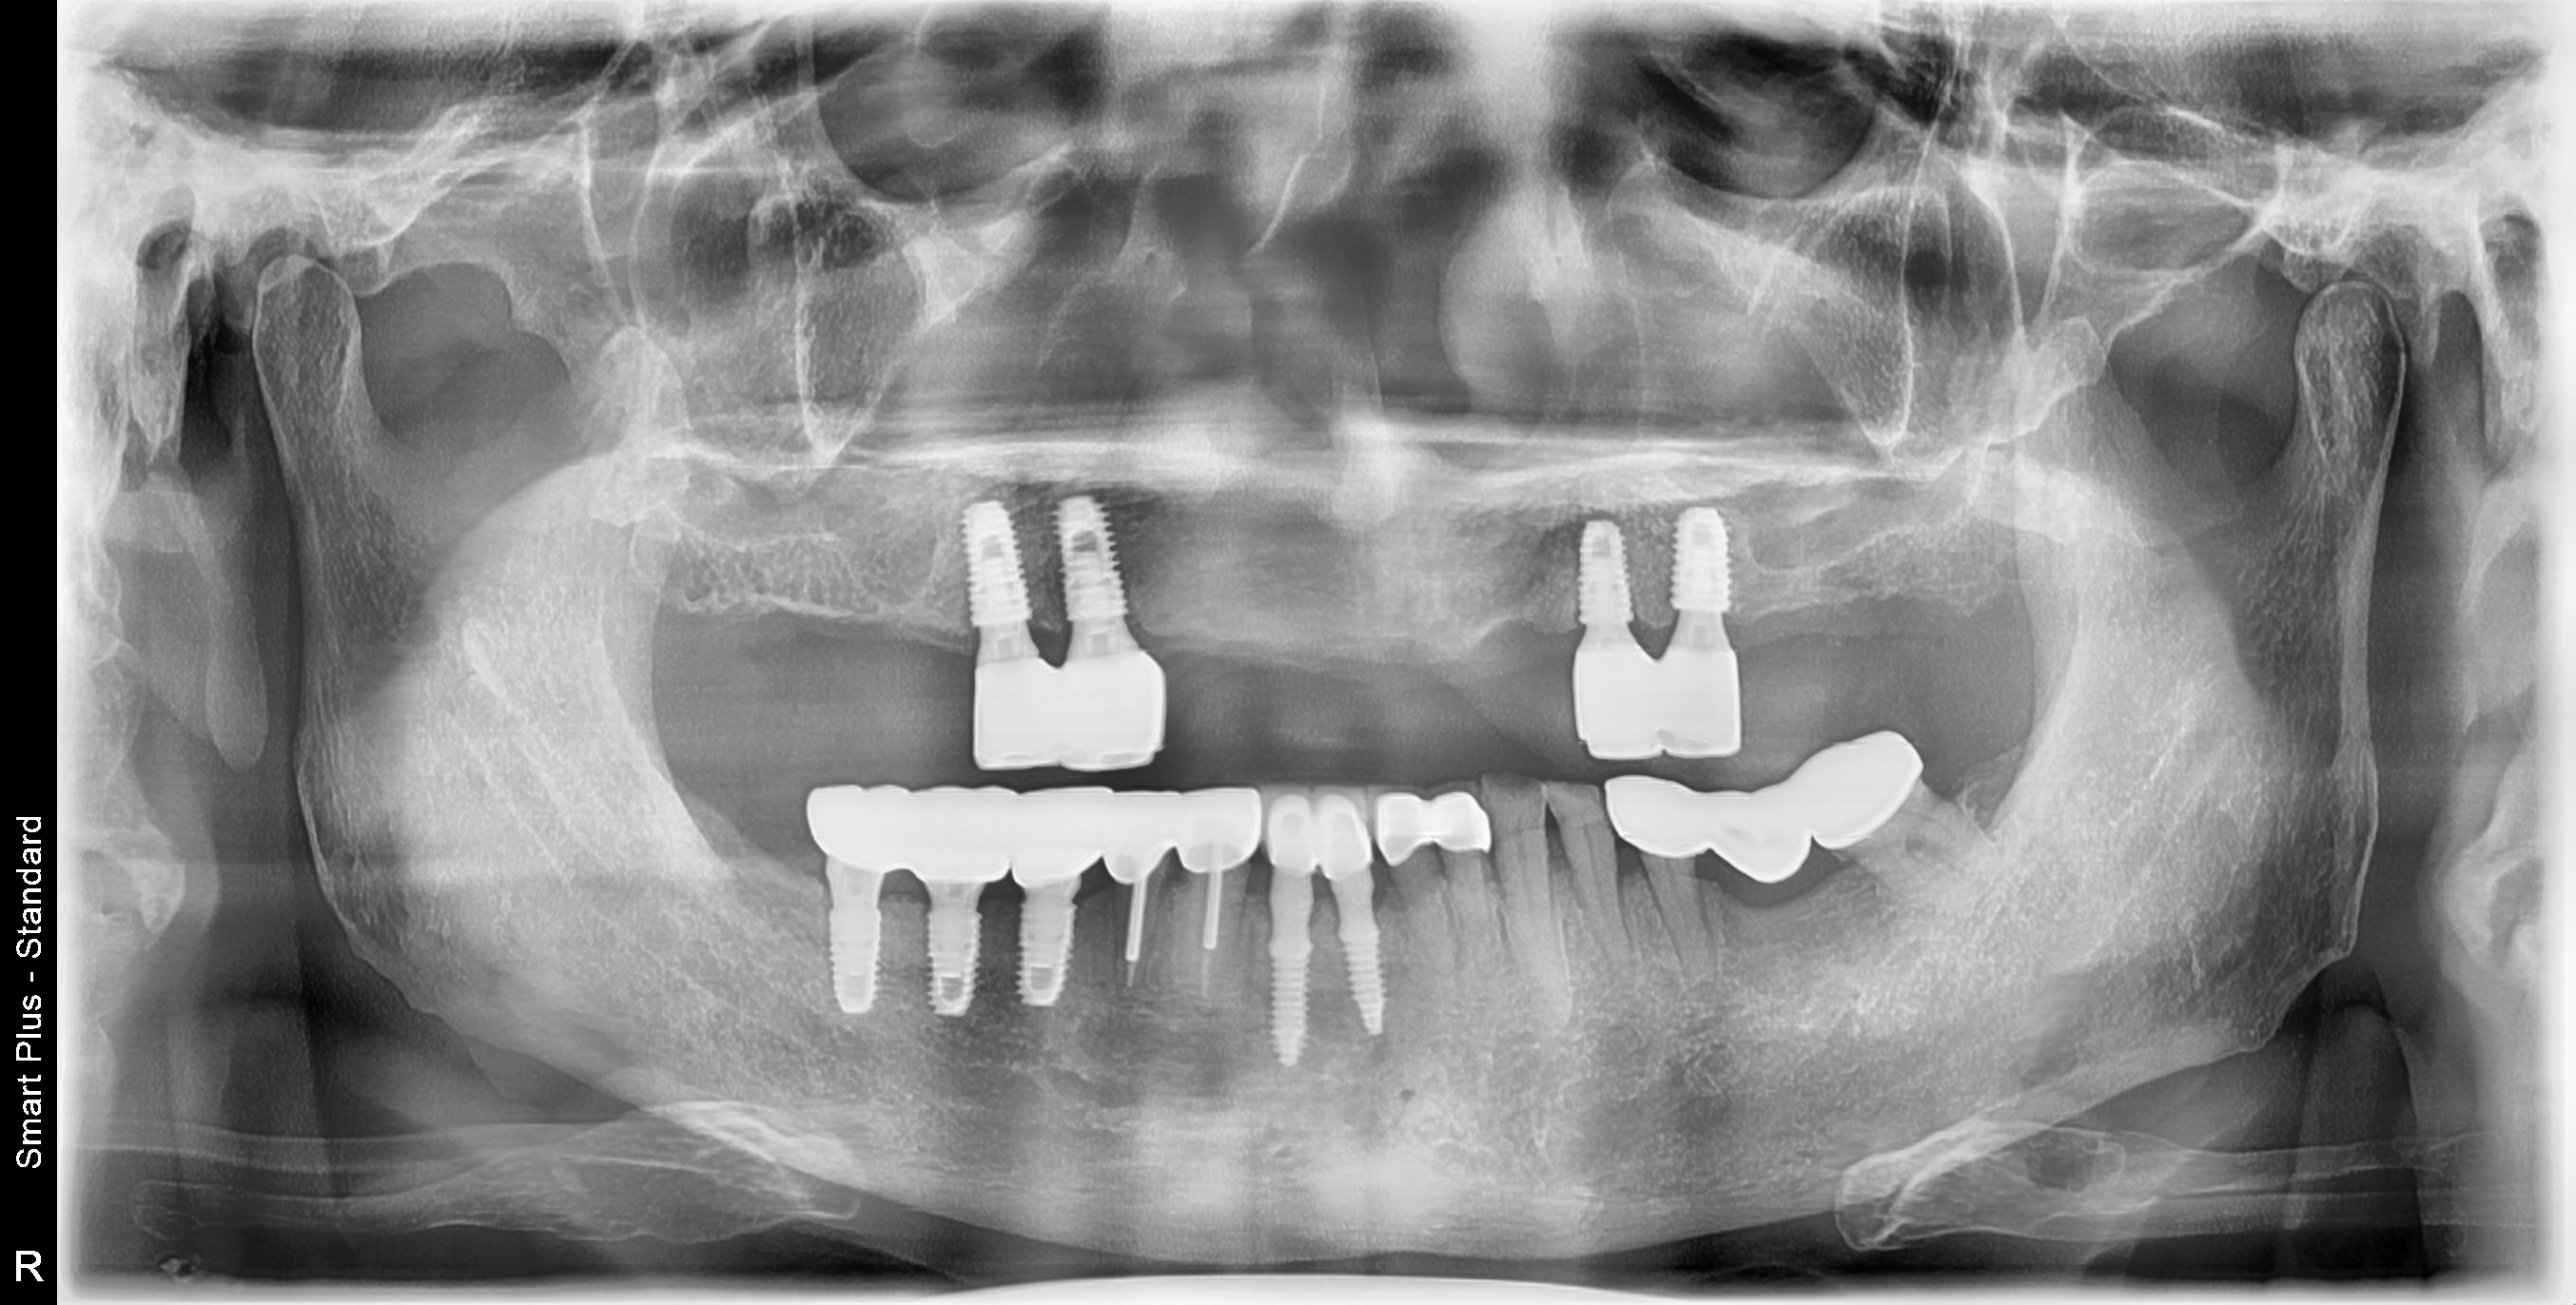

[임플란트] 제목 : 임플란트 지지 틀니

상악 임플란트 지지 틀니와 하악 고정식 보철의 만남.